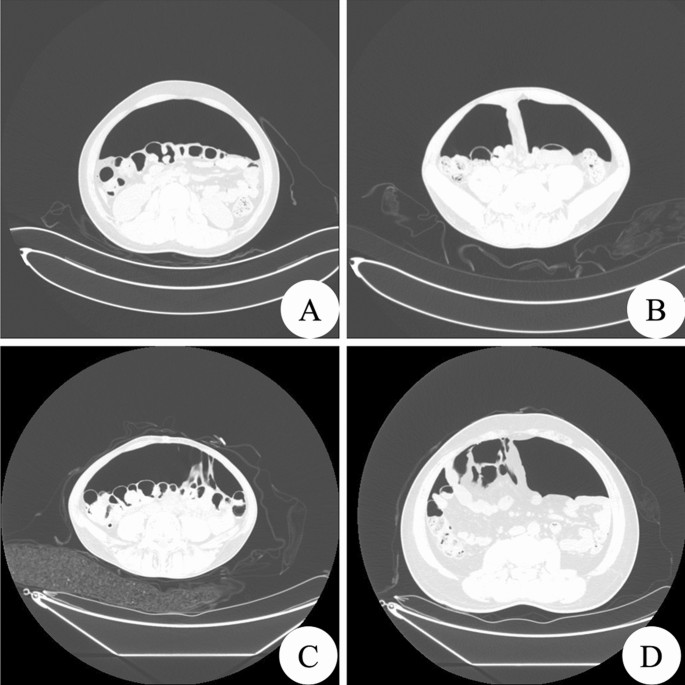

A total of 43 patients showed a normal pneumoperitoneal space, of whom 15 patients were confirmed by surgery to have abdominal adhesions. The axial view of the normal artificial pneumoperitoneal image showed a bulging abdomen; the visceral peritoneum was separated from the peritoneum of the abdominal wall, the peritoneal cavity was full of gas, the pneumoperitoneal space was clearly displayed, the abdominal wall was thin and uniform, and the inner surface was smooth. The internal organs of the abdominal cavity were spread out evenly. There was a broad semi-moon-shaped pneumoperitoneal space between the abdominal internal organs and the anterior abdominal wall. The intestinal tube was not expanded, and the wall was thin and evenly circular. The sagittally reconstructed image showed that the pneumoperitoneum had the shape of a long knife. Oblique images of the normal artificial pneumoperitoneum showed that the abdominal bowel tended towards one side under the action of gravity. The space between the bowel and the oblique side of the abdominal wall was increased due to the filling of gas. At this time, the relationship between the bowel and the lateral abdominal wall was clearly displayed. In the prone position, the abdominal internal organs were in close contact with the anterior abdominal wall under the action of gravity, and air filled the space between the posterior abdominal wall and the visceral peritoneum. The abdominal internal organs were separated from the posterior peritoneum. At this time, the relationship between the abdominal internal organs and the posterior abdominal wall was clearly displayed (Fig. 1).

Normal pneumoperitoneal space. (A) Shows a normal horizontal axial artificial pneumoperitoneal image (lung window). The peritoneum of the visceral wall is separated, and there is a half-moon-shaped pneumoperitoneal space. The arrows show that the paracolic sulci on both sides are clear and sharp. (B) Shows a normal sagittal image of artificial pneumoperitoneum. The pneumoperitoneal space has the shape of a long knife, and the peritoneum of the visceral wall is clearly separated. (C) Shows the image of a normal oblique artificial pneumoperitoneum, the abdominal organs are tilted to one side, the contralateral pneumoperitoneum is clear, and the abdominal organs and lateral abdominal wall are clearly displayed. (D) Shows the image of the artificial pneumoperitoneum in the normal prone position. Gas fills the space between the posterior abdominal wall and the visceral peritoneum. The relationship between the abdominal organs and the posterior abdominal wall is clearly shown.